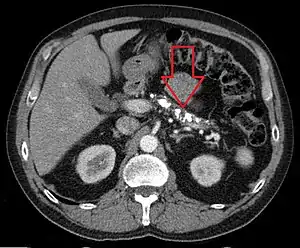

| Axial CT showing multiple calcifications in the pancreas in a patient with chronic pancreatitis | |

On CT scan, pancreatic and bile duct dilatation, atrophy of pancreas, multiple calcifications of the pancreas, and enlargement of pancreatic glands can be found.[14]